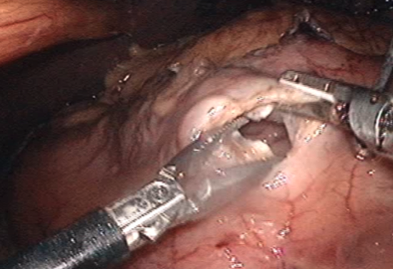

胃、食道それぞれにカッター付ホチキスを入れるための穴を開けます。

- 2

カッター付ホチキスをそれぞれの穴に入れて切り離すと、胃と食道がつながります。

その後で食道を切り離し、胃の上3分の1が切除されました。 - 3